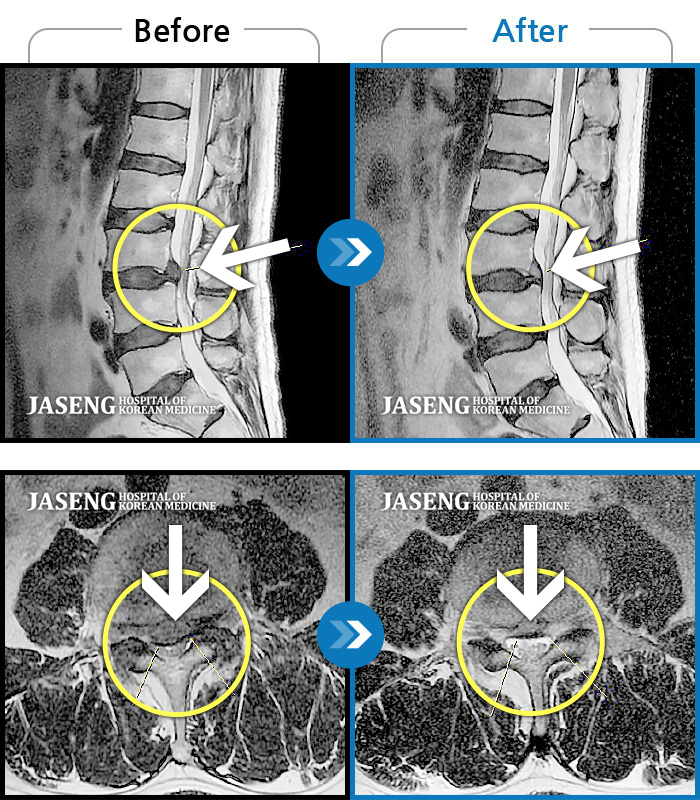

Before

After

환자에게 사전 동의를 받아 동일 조건에서 촬영되었습니다.

개인에 따라 치료 후 부작용이 발생할 수 있으니 의료진과 상담 후 치료를 진행하시기 바랍니다.